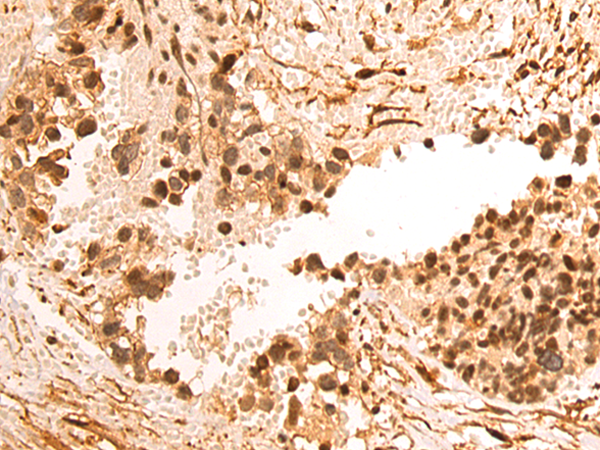

分类: 科研抗体货号: P12486别名: CDX3; CDX-3; CDX2/AS应用: WB,IHC反应种属: Human, Mouse